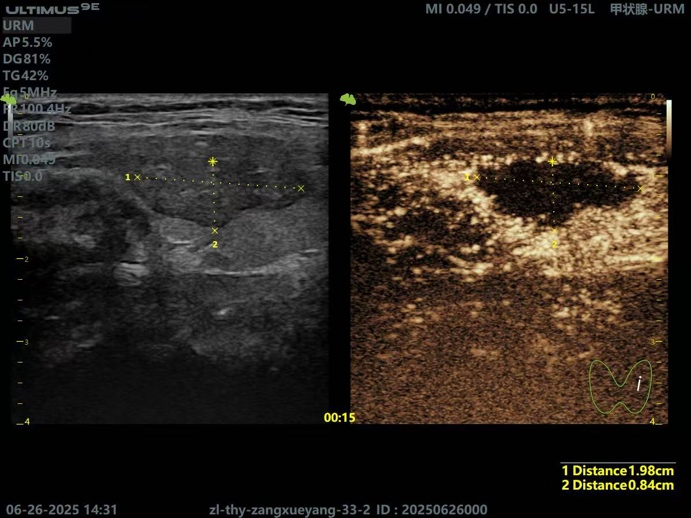

随后,在叶欣的指导下,副主任医师陈守华及主任医师王爱光为患者实施了甲状腺癌微波消融术,手术仅耗时15分钟,术中及术后无出血,通过精心的治疗与护理,患者术后3天康复出院。术后1月复查甲状腺超声造影提示病灶完全消融,且甲功五项指标正常,患者及家属对于治疗效果非常满意。

甲状腺左侧叶结节消融术后所见

超声造影术后复查